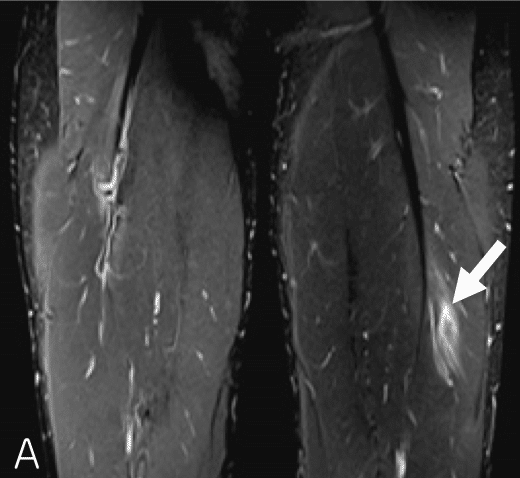

◉Ⅰ型の例

(奥脇 透:大腿二頭筋肉ばなれの MRI 分類、臨床スポーツ、2019より引用)